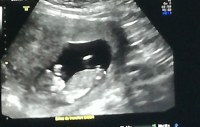

Pour mon bébé, la semaine passée, j'ai fait l'écho à 22 sa et 6 jours, et elle pesait 440 g La première était déjà une crevette !Poids moyen foetus 32 sa Septième mois de grossesse (29 SA 32 SA) 29 SA / 27 SG 34 cm 1 kg 30 SA / 28 SG 35 cm 1,1 kg 31 SA / 29 SG 36 cm 1,3 kg 32 SA / 30 SG 37 cm 1,5 kgCopier le lien Mesdames, si vous pouviez regardez sur vos compte rendus d'écho pour voir combien pesait votre baby à ce stade là, ça serait gentil La gygy m'a dit qu'elle était dans la normale mais légèrement plus petite (en poids)

j'ai eu ma pesée à 22 SA et demi et j'étais à 6kg, le gygy m'a dit que c'était bien, juste un kilo de trop!Poids et taille Votre bébé mesure maintenant 23 cm environ, et pèse entre 380 g et 400 g Son corps commence à prendre des dimensions plus harmonieuses Sa tête semble moins disproportionnée par rapport au reste de son corps Ses muscles, eux, se renforcent Les mouvements de bébé Votre bébé à la e semaine de grossesse – 22 SA A la semaine de grossesse – 22 SA, votre bébé s'éclate dans 500 cm3 de liquide amniotique qu'il boit de plus en plus, hummm !

Bonjour, Je trouve le poids de ma puce hallucinant par rapport aux données que l'on peut lire sur le net ou dans les bouquins de grossesse alors comme c'est bébé 1 pour moi et que ça m'inquiète un peu ayant une amie qui vient d'accoucher d'une "crevette" de 45kgs je viens voir si certaines d'entre vous peuvent m'aider à "comparer" en me donnant le poids de leur bébinou à 23 SA 21 semaines de grossesse Lors de la 23ème semaine d'aménorrhée ou 21ème semaine de grossesse, la peau de votre bébé est encore si translucide qu'on pourrait y voir au travers À partir de maintenant et alors que le cinquième mois de la grossesse arrive, le poids du fœtus va augmenter considérablement chaque semaine etC'est la 22ème semaine de grossesse et le bébé mesure 26 cm Le poids du bébé à 24 sa est d'environ 500 g Avec un périmètre crânien d'environ 6 cm, sa tête est encore volumineuse

A 22 sa Bebe faisait 492g et 26 cm!Poids normal foetus 32 sa Forum Grossesse / Bébé;